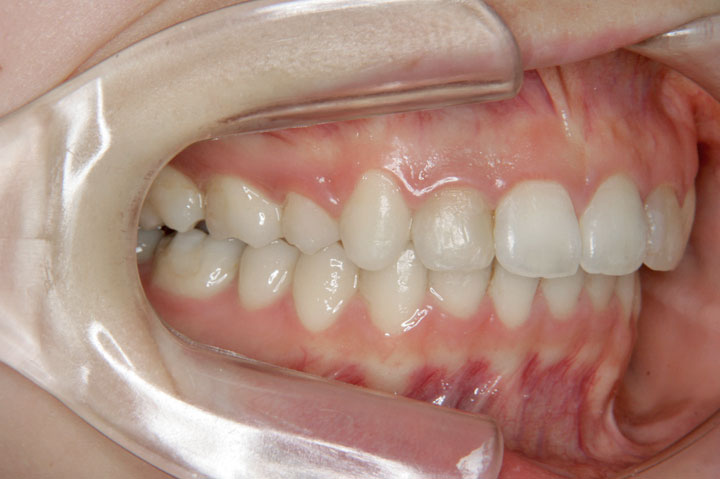

上顎前突(出っ歯)

叢生(乱ぐい歯)

上顎前歯の前突感と歯のでこぼこを気にされて来院された成人の患者さんです。前突傾向を強く認められたため、上顎小臼歯を抜歯させていただきデーモンシステムで治療させていただきました。また、後戻りを防ぐための保定装置は、上下ともボンデッドワイヤーとリテーナーを利用いただいております。